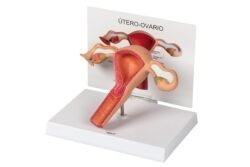

Modelo anatómico del úteroovario femenino